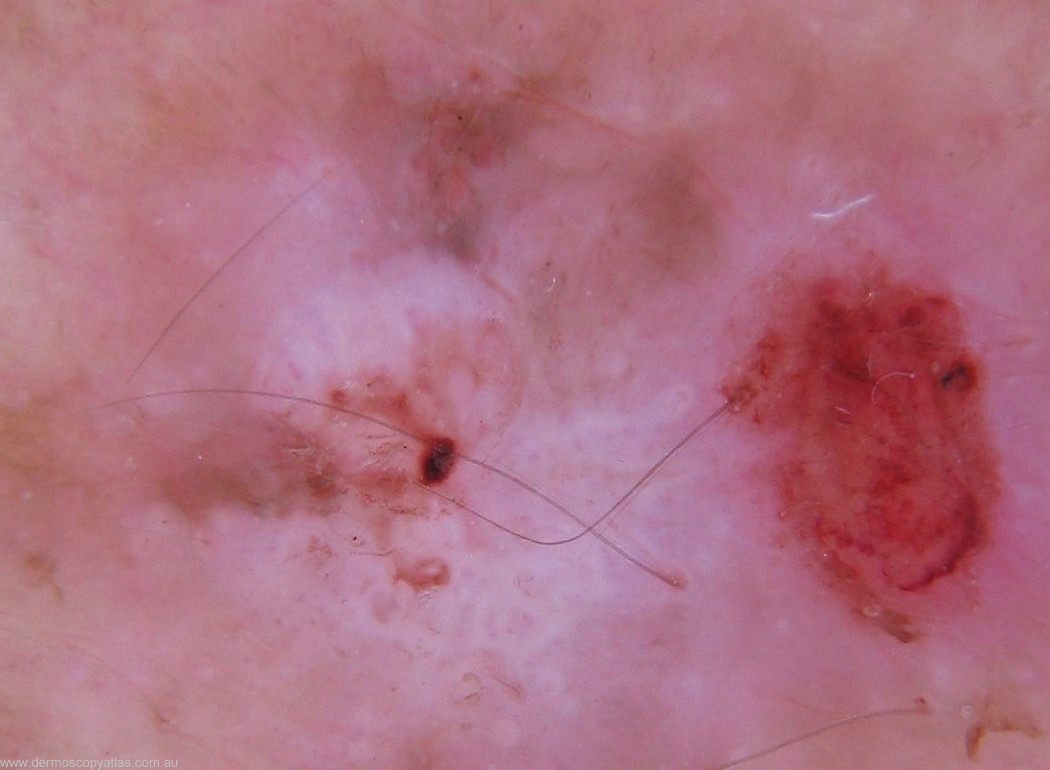

Case 7 67 y.o man presented for skin check. Papule upper back,level of T2 left paravertebral area. He was unaware of this lesion.

Question: What is your provisional diagnosis of this lesion? (Consider Hypomelanotic melanoma,Hypertrophic solar keratosis,Squamous cell carcinoma in situ,Nodular basal cell carcinoma and irritated fibroepithelioma.)

Answer: Traumatised hypertrophic solar keratosis